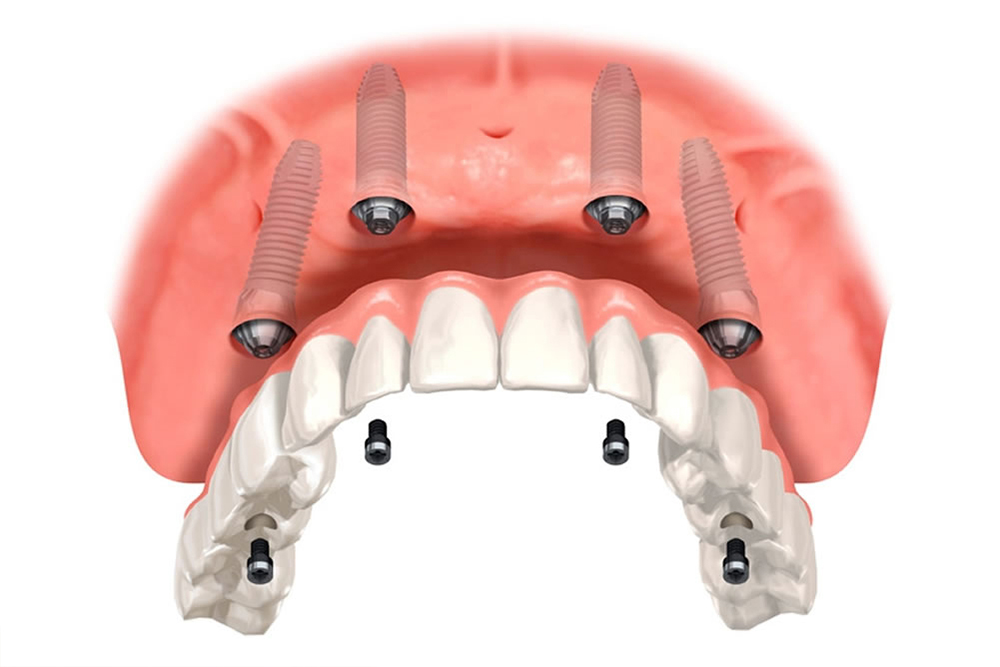

体への負担を抑えたオールオン4インプラントにも対応

巣鴨S歯科矯正歯科では、4本のインプラントで片顎全ての歯を支えるオールオン4という特殊なインプラント治療にも対応しております。

巣鴨S歯科矯正歯科では、4本のインプラントで片顎全ての歯を支えるオールオン4という特殊なインプラント治療にも対応しております。

無歯顎の場合、全ての歯を1本ずつインプラントにするよりも費用が抑えられ、さらに手術の回数も少なくて済むため、体への負担も抑えることができます。